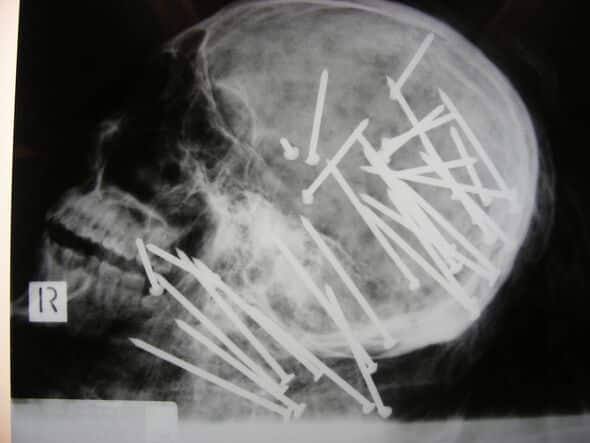

Law enforcement revealed a gruesome X-ray of his skull to try and find the perpetrator who used a powerful nail gun to fire the nails, measuring up to 3.3 inches in length, into the victim’s head and neck.

Two weeks before the children discovered Chen’s corpse, a male friend reported him as missing. Beresford mentioned that 34 nails had entered “mainly into the head region” at very close range, discharged from an 85mm nail gun.